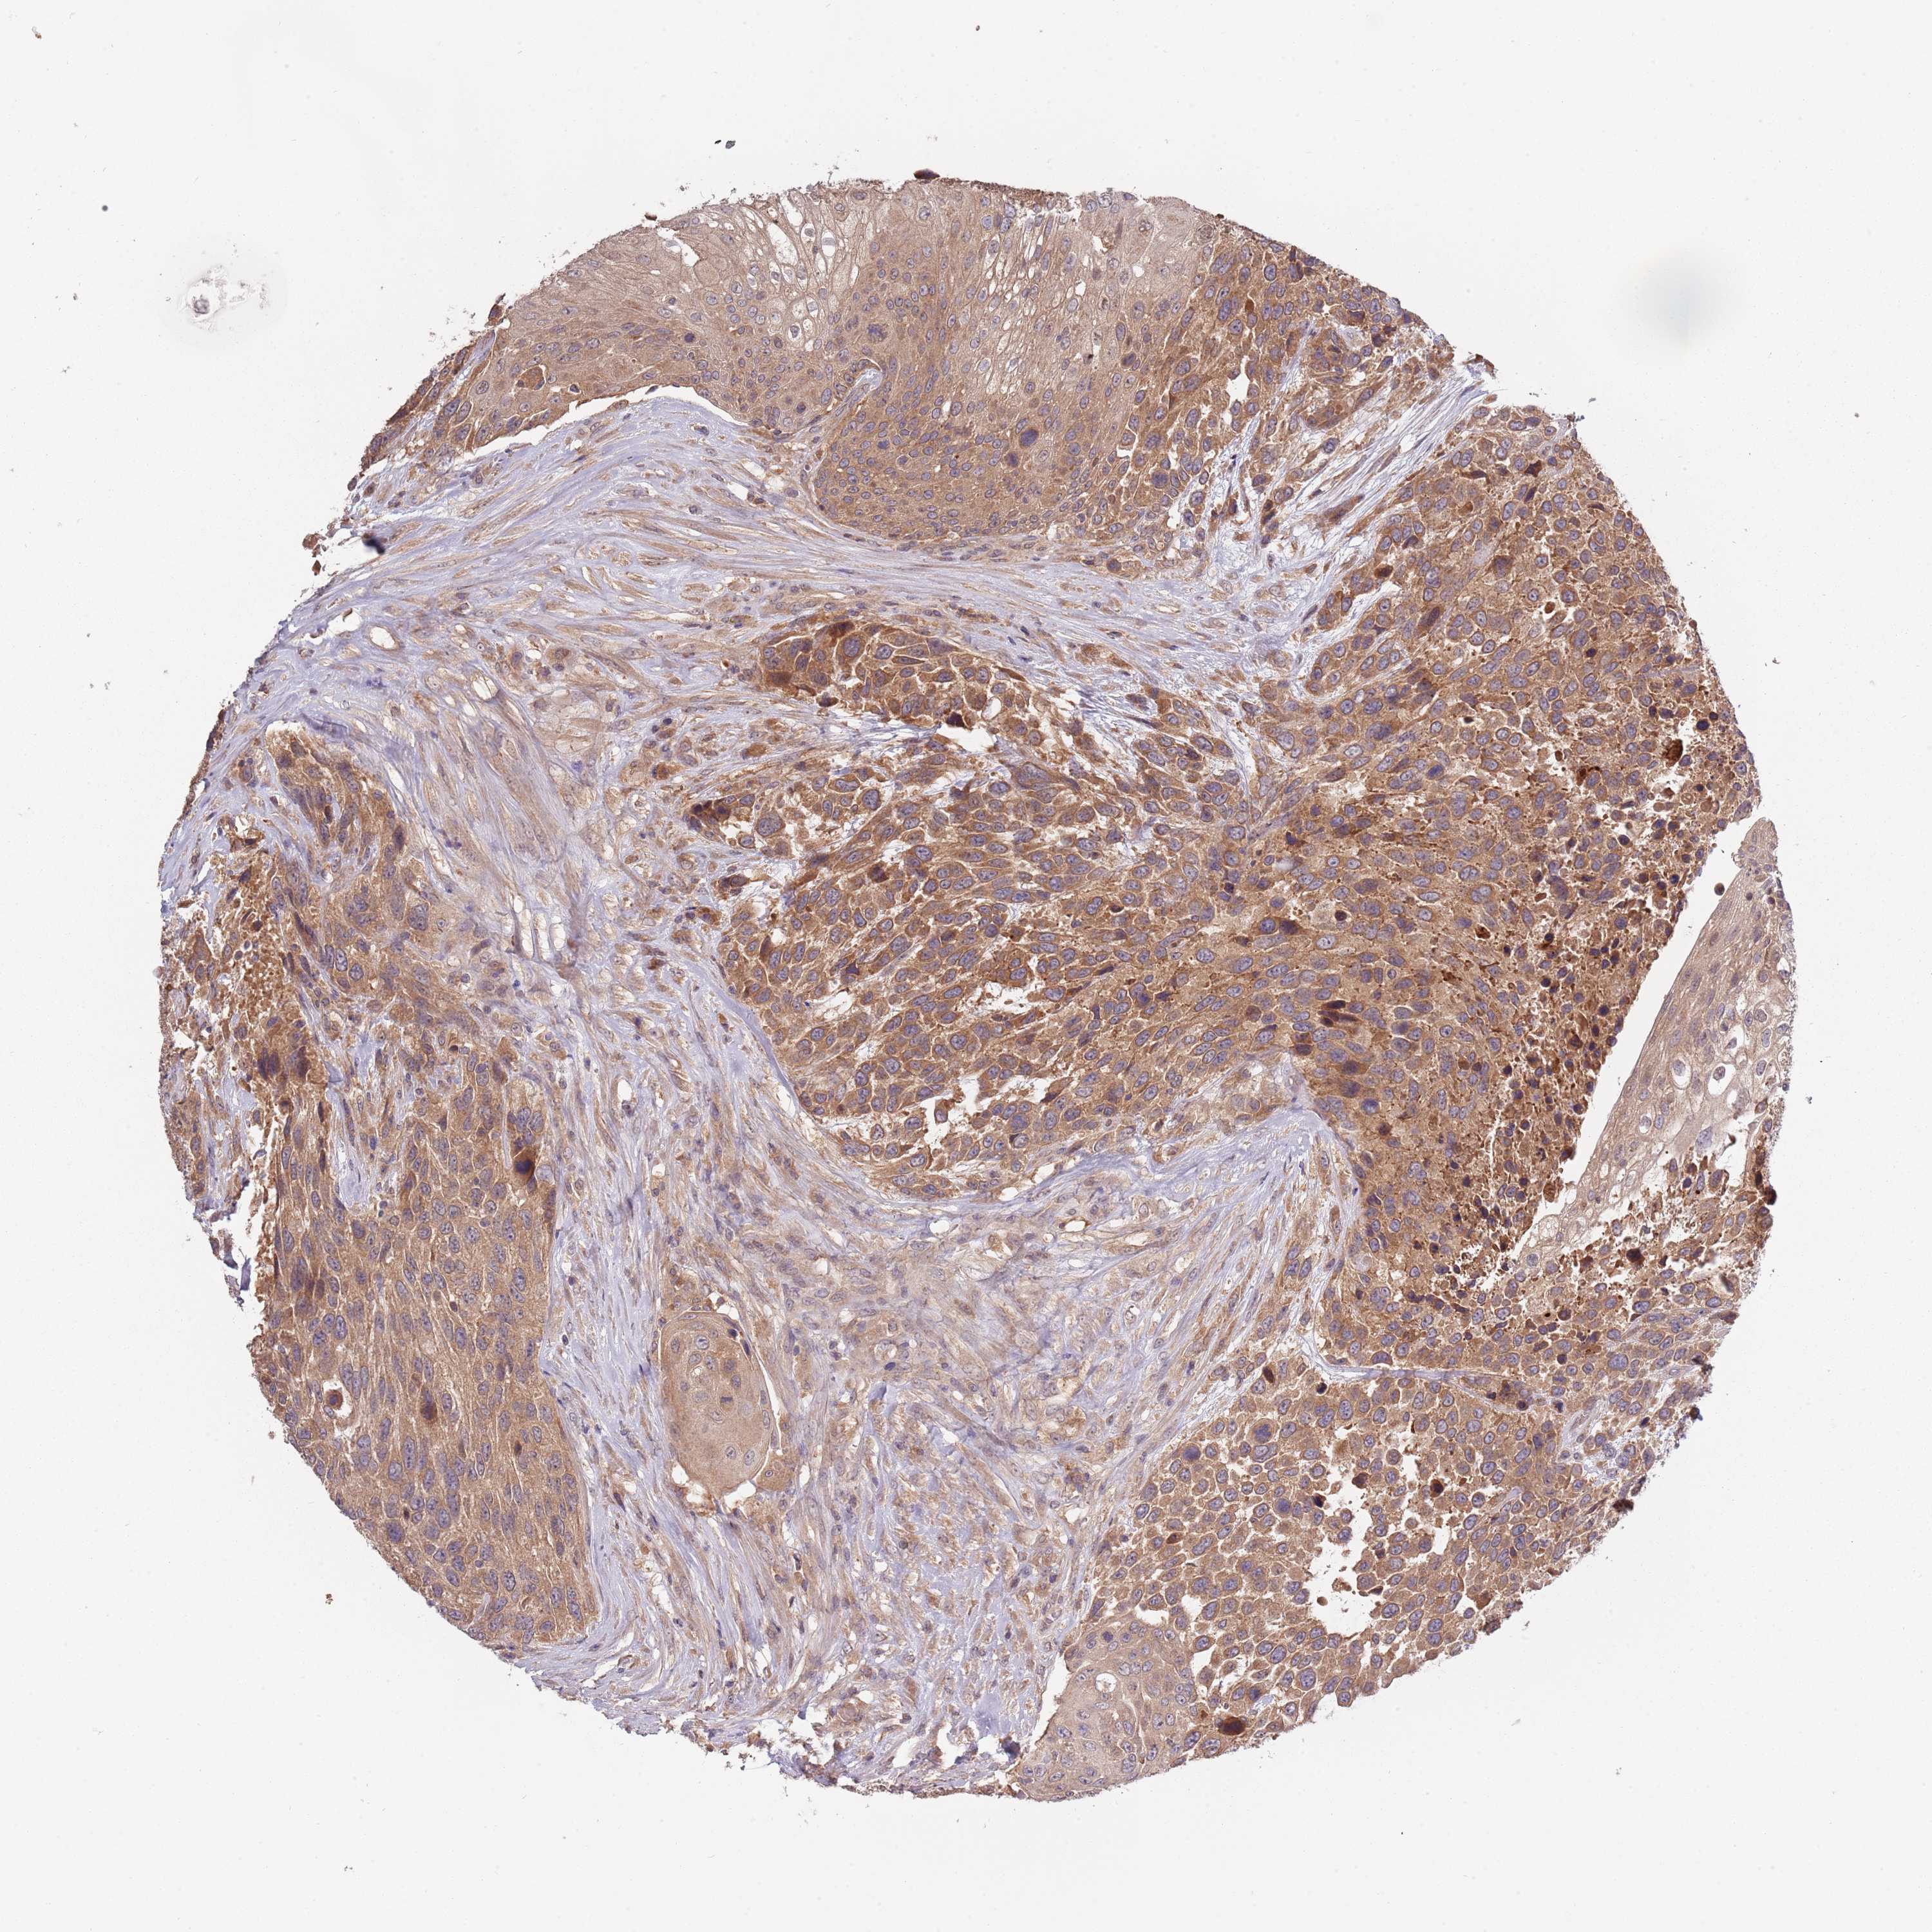

UROTHELIAL CANCER - Protein expressioni

A mouse-over function shows sample information and annotation data. Click on an image to view it in a full screen mode. Samples can be filtered based on level of antibody staining by selecting one or several of the following categories: high, medium, low and not detected. The assay and annotation is described here.

Note that samples used for immunohistochemistry by the Human Protein Atlas do not correspond to samples in the TCGA dataset.

Antibody stainingi

Antibody staining in the annotated cell types in the current human tissue is reported as not detected, low, medium, or high, based on conventional immunohistochemistry profiling in selected tissues. This score is based on the combination of the staining intensity and fraction of stained cells.

Each image is clickable and will lead to virtual microscopy that enables deeper exploration of all samples and also displays staining intensity scores, fraction scores and subcellular localization as well as patient and tissue information for each sample.

Antibody HPA044365

Staining

High

Medium

Low

Not detected

Intensity

Strong

Moderate

Weak

Negative

Quantity

>75%

75%-25%

<25%

None

Location

Nuclear

Cytoplasmic/membranous

Cytoplasmic/membranous,nuclear

Urothelial carcinoma, Low grade

Urothelial carcinoma, High grade

Urothelial carcinoma, NOS